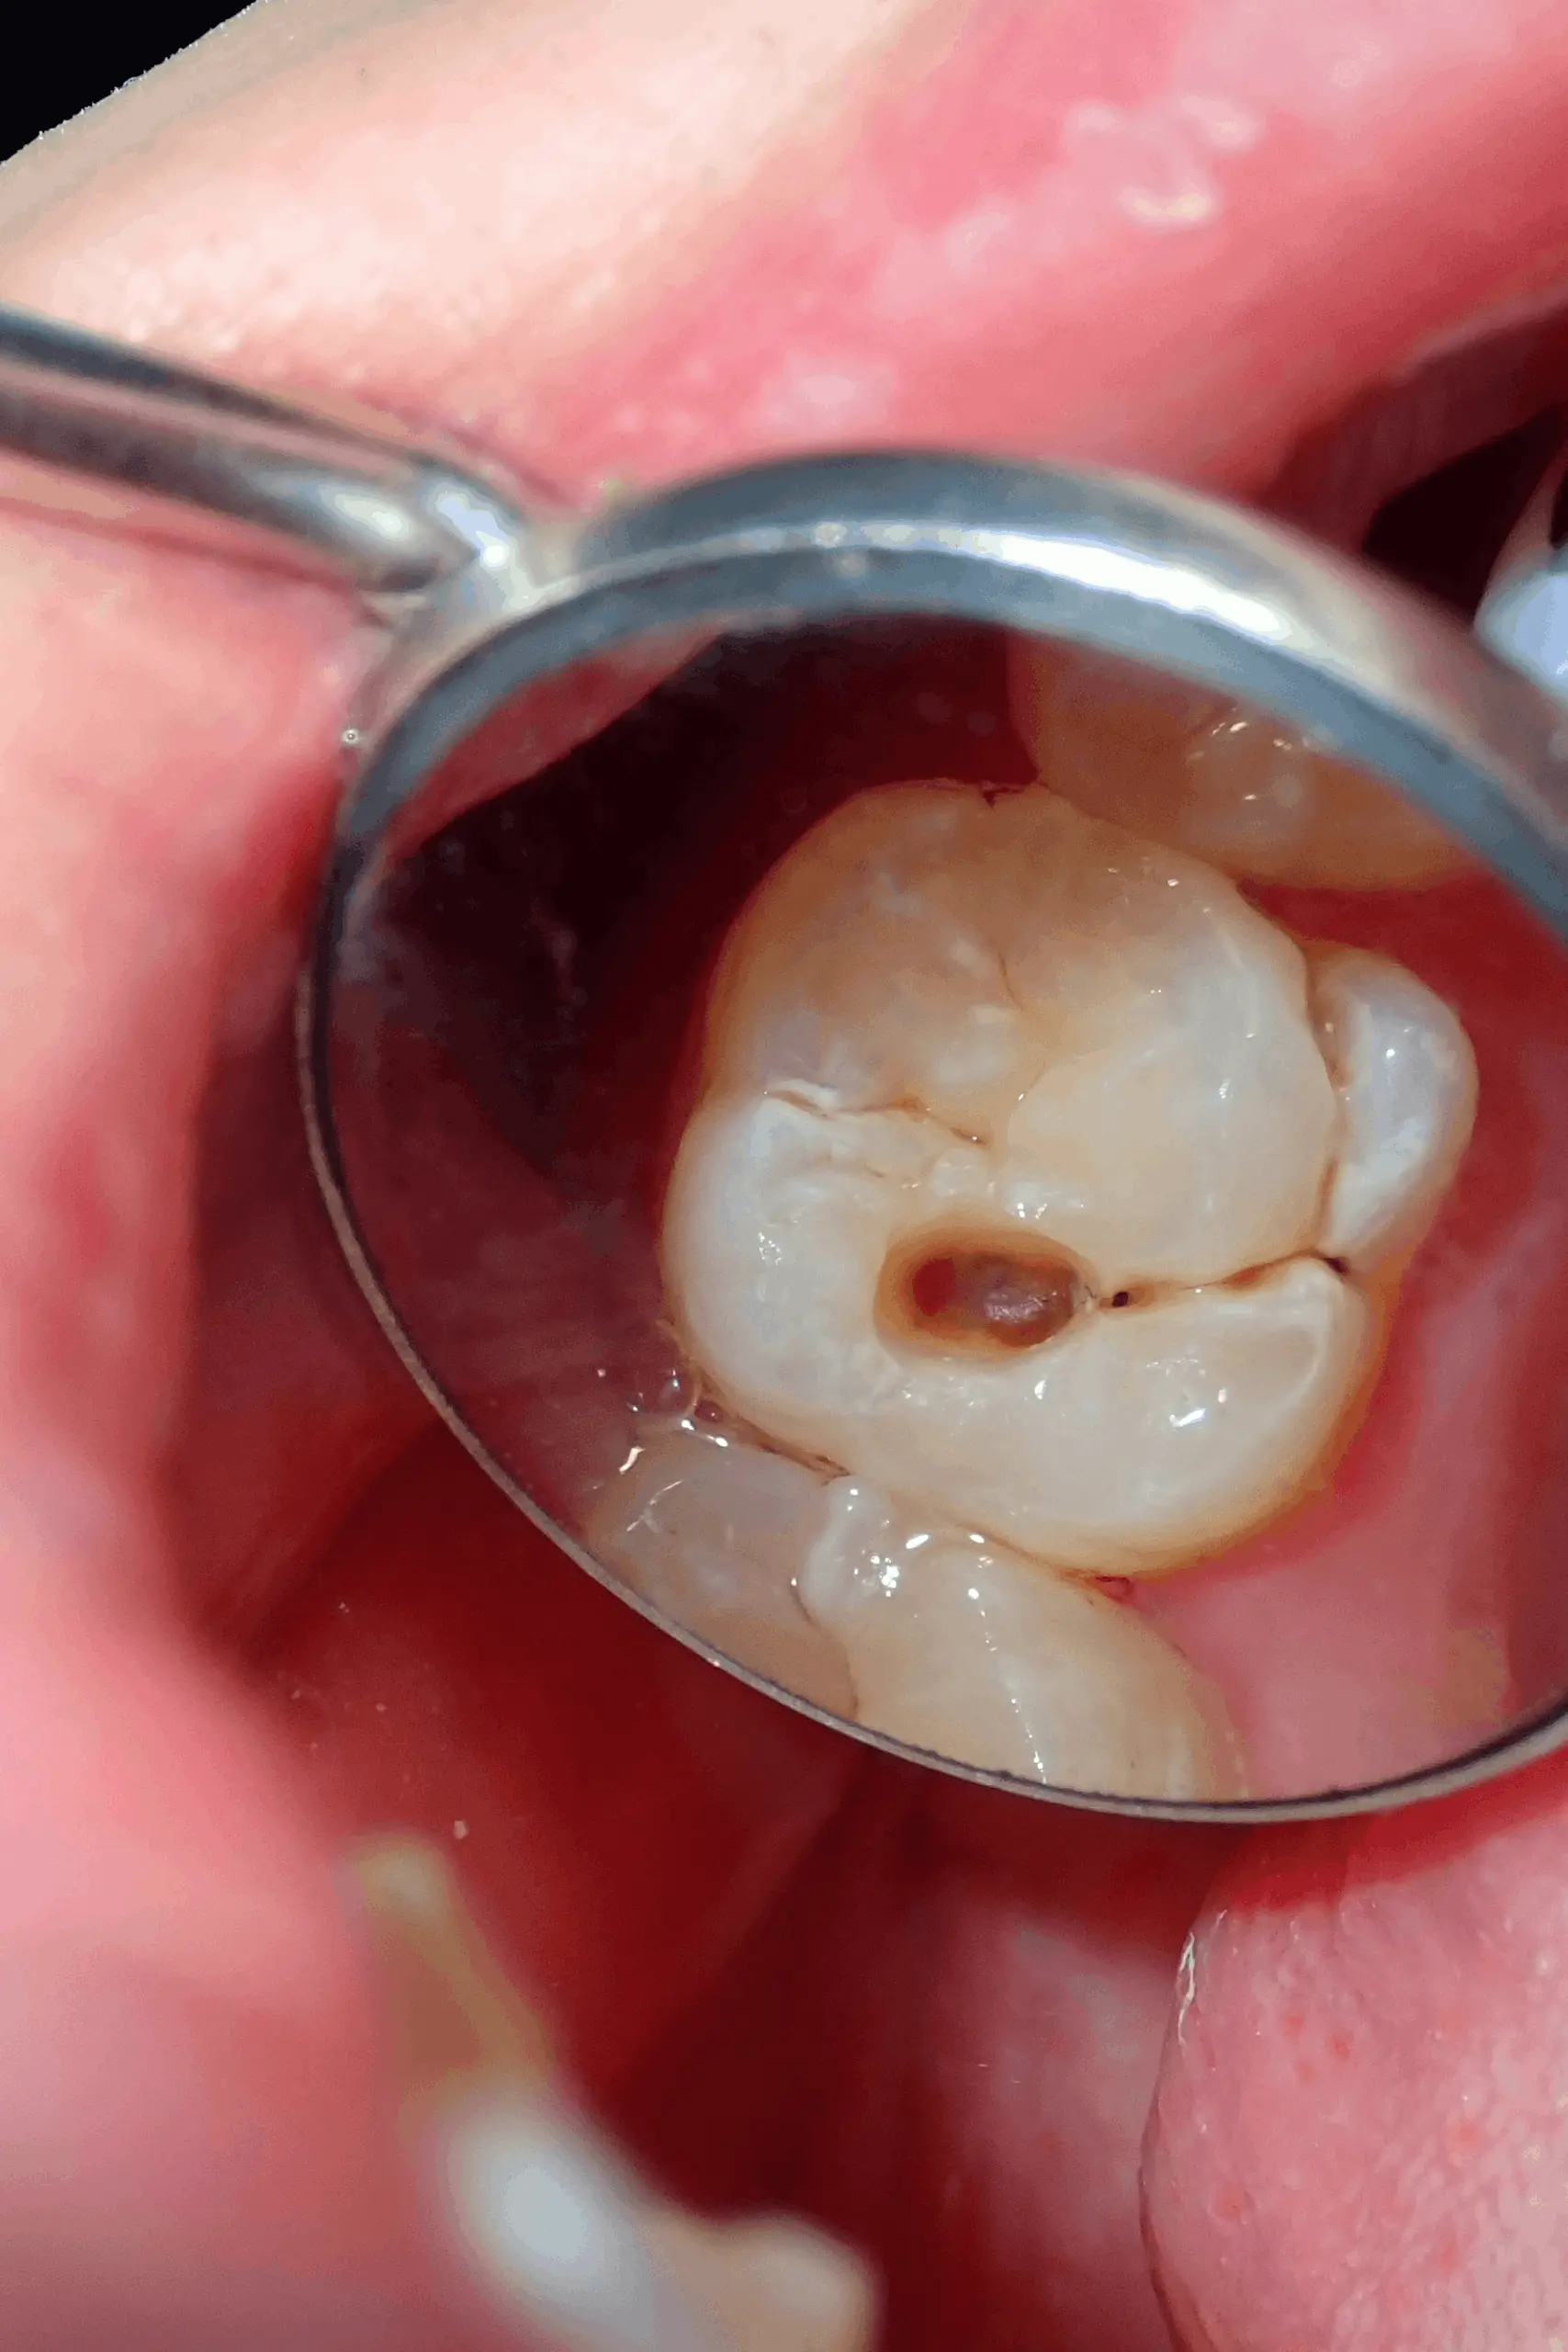

Tooth decay (cavity)

Decay often starts small and without any symptoms. It's usually spotted during a routine check-up or on an X-ray before you feel a thing, which is exactly why regular visits matter.

- Often no pain at all in the early stages

- A visible dark spot or hole in the tooth

- Mild sensitivity to sweet food or cold drinks

- A rough or catching edge you can feel with your tongue

- Picked up on X-ray before any visible signs appear